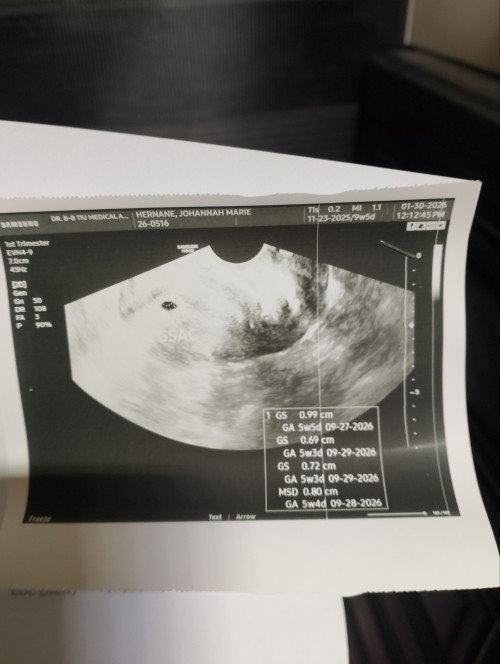

Hello fellow mommies, I am 9 weeks pregnant and may ubo ako na mag 1 month na. 1st week ng ubo, di ako nakapagpacheck up kasi nasa bakasyunan. 2nd week, niresetahan ako ng Cefuroxime tablet ng OB ko. Tinake ko for 7days. 3rd week, nagpacheck up naman ako sa Pulmo kasi di nawala sa Cefuroxime ubo ko and sinuggest na rin ng OB ko na pulmo na. Pinagnebulize ako ng pulmo ko kasi yun lang ang safe for pregnant daw. I am taking Salbutamol, Fluimucil, and 0.9% Saline Solution. Lahat yan nebule. Then pinagantibiotic ulit ako. This time cefixime tablet naman. Ang worry ko lang is, makakaapekto kaya ang mga tinetake ko sa development ni baby? Possible kaya mahawa din si baby sa ubo ko? Praying ako na gumaling na ako at maging normal padin ang lahat. Huhu. Would like to know your similar experiences, mommies. Btw, non stop din ang folic acid ko and duphaston along with the other meds na tinetake ko. #askmommies #Needadvice